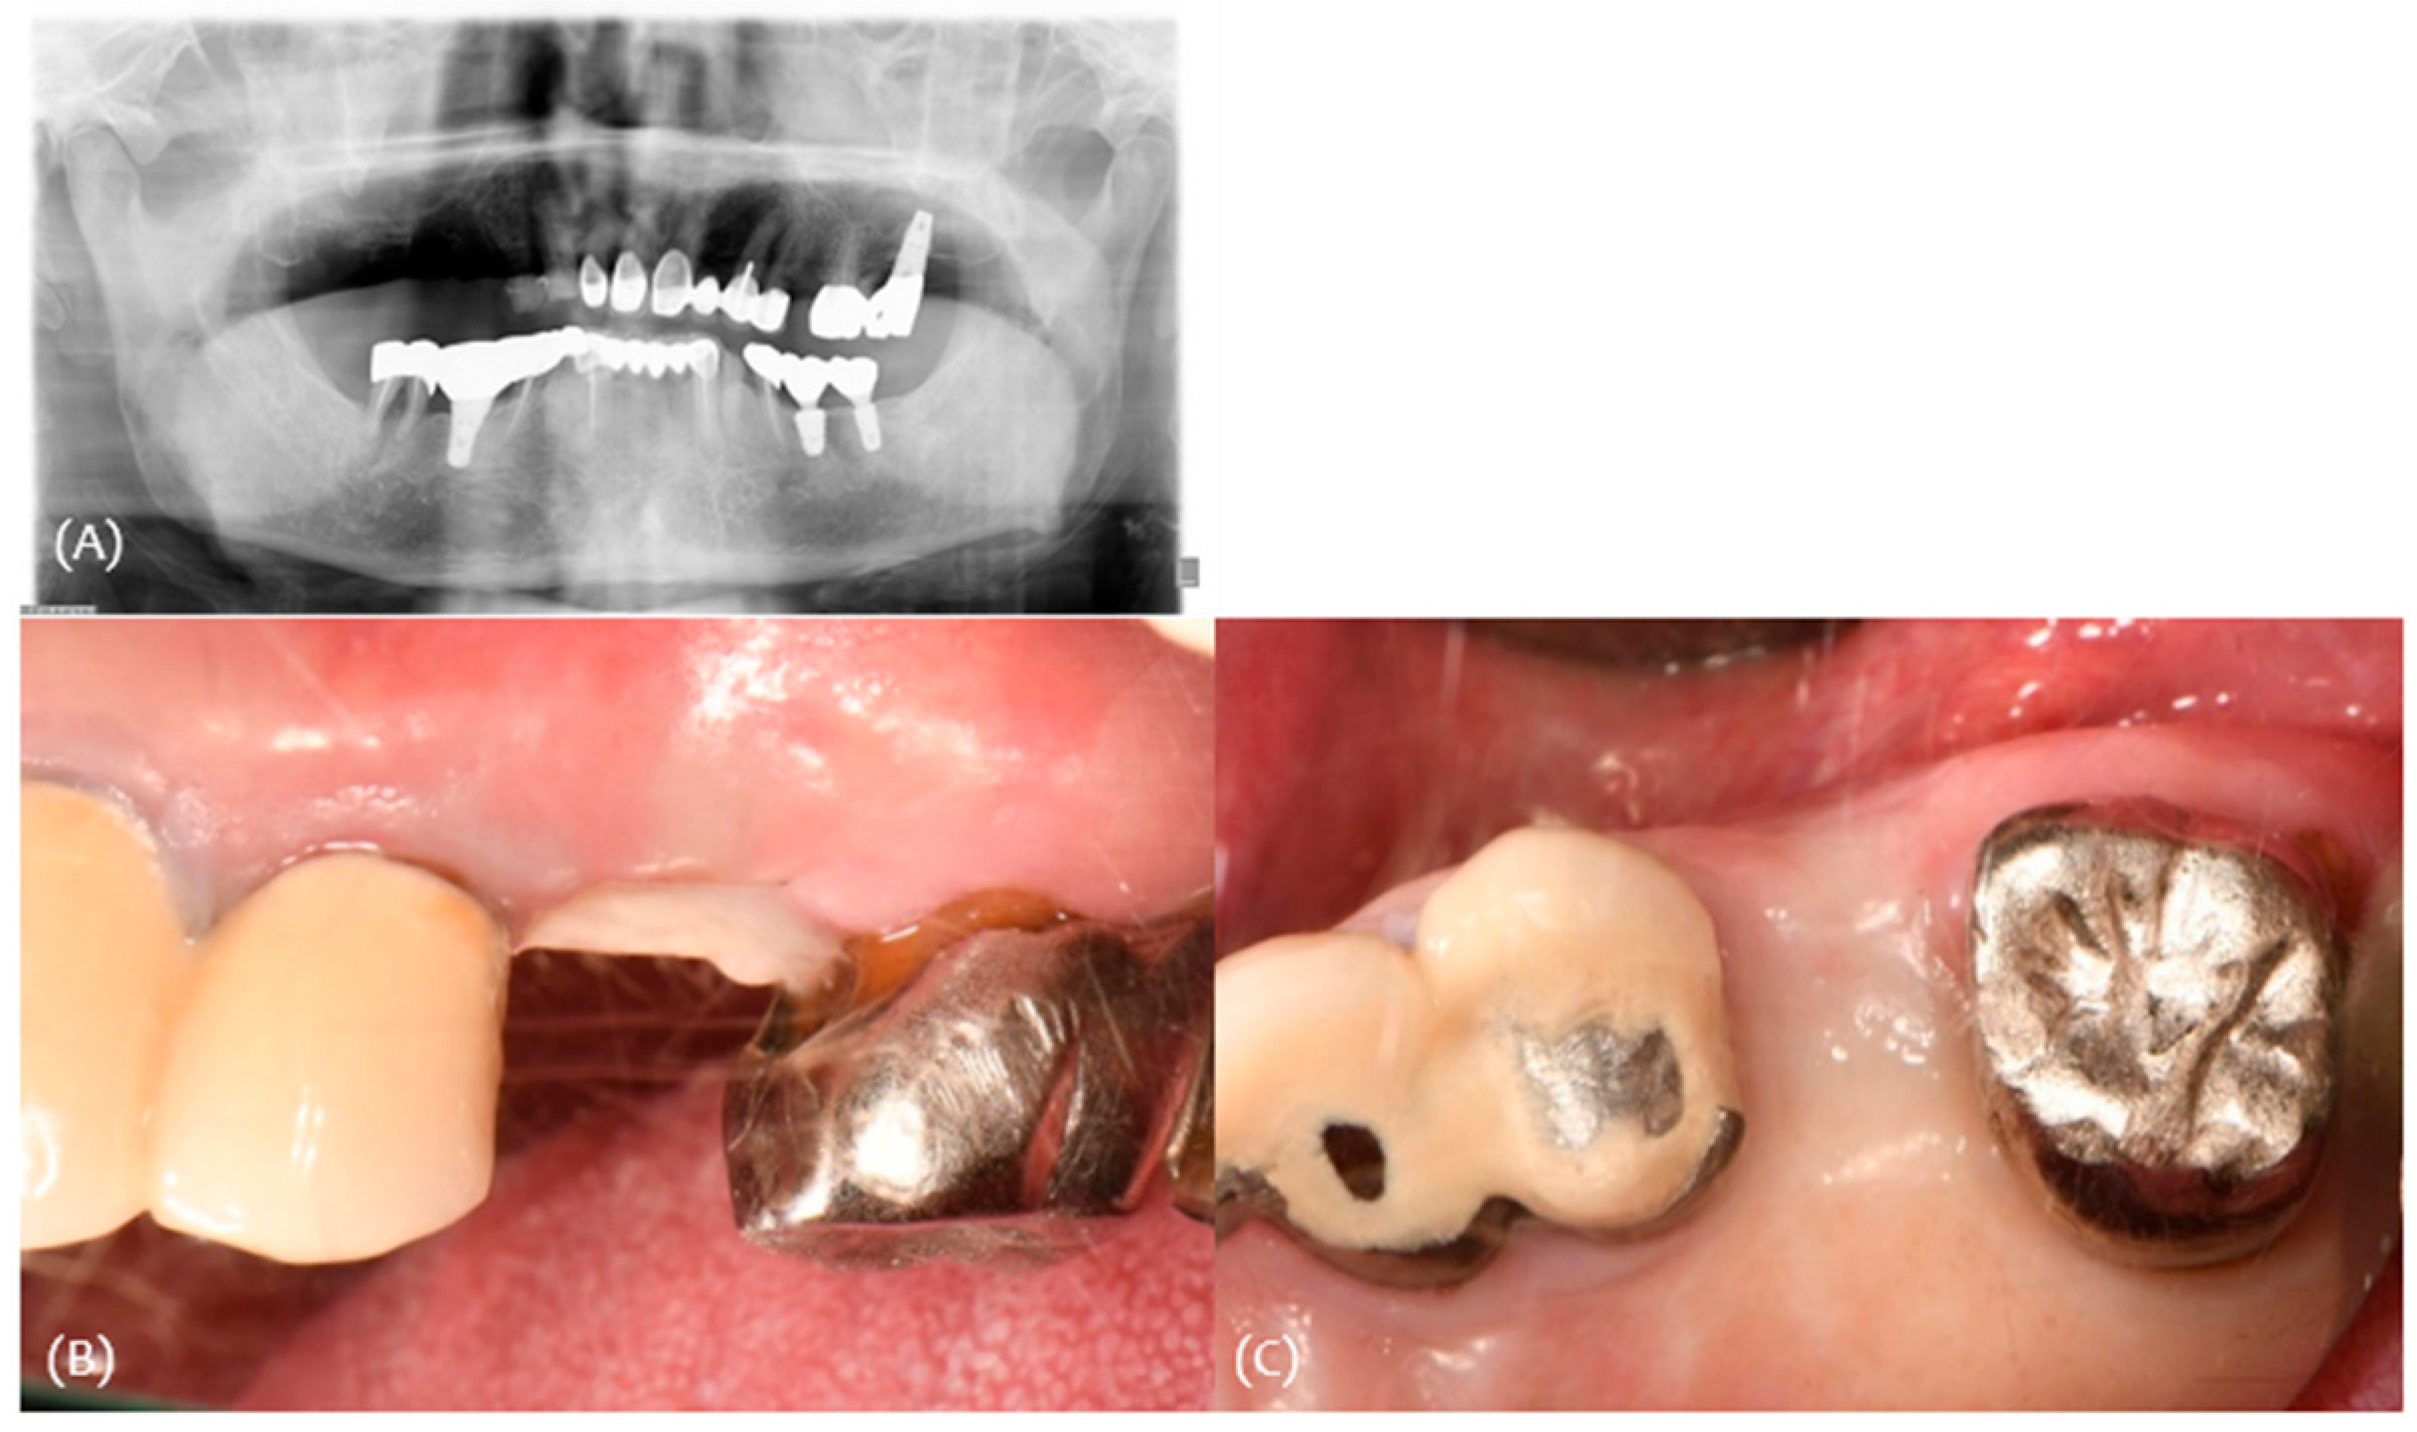

3.2. Case 2

| #24 | #25 | #26 | |

|---|---|---|---|

| Classification (Seibert) | Class I | ||

| Amount of maximum concavity (mm) | 1.8 | ||

| Buccal pocket depth (mm) | 333 | 446 | |

| Palatal pocket depth (mm) | 223 | 346 | |

| Bleeding on probing | - | - | |

| gingival recession (mm) | 000 | 002 | |

| Keratinized tissue Width (mm) | 5 | 4 | 5 |

| Site | Pre-Op Concavity (mm) | Increased Buccal Soft Tissue Volume 2 Weeks After Op (mm) | Increased Buccal Soft Tissue Volume 4 Months After Op (mm) |

| Distal | 1.2 | Δ 0.963 | Δ 0.409 |

| Disto-middle | 1.5 | Δ 1.52 | Δ 0.419 |

| Middle | 1.8 | Δ 1.39 | Δ 0.606 |

| Mesio-middle | 1.6 | Δ 1.13 | Δ 0.511 |

| Msesial | 1.1 | Δ 0.351 | Δ 0.686 |

| Average | 1.44 | Δ 1.0708 | Δ 0.5262 |